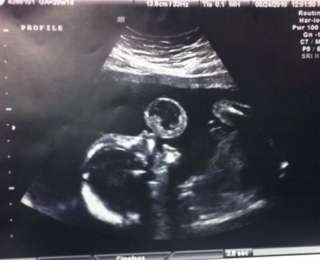

Тамми Гонзалес из США была на 17 неделе беременности, когда врачи обнаружили нечто необычное вовремя очередного сеанса УЗИ. Казалось, будто малыш в утробе надувает пузырь. Увиденное, как бы там ни было, оказалось тератомой, редкой разновидностью раковой опухоли. Врачи рекомендовали Тамми немедленно провести операцию по удалению образования, пока малыш еще находится в утробе. Иначе девушка могла потерять ребенка.

Тамми, разумеется, согласилась - для нее не было ничего важнее здоровья и жизни своей малышки. Через две недели доктора решились на операцию, которую никогда раньше не проводили. Во время всего хирургического процесса девушка оставалась в сознании, наблюдая за тем, как медики делают надрез на ее животе, вводят внутрь специальную камеру и с помощью лазера удаляют опухоль. Через пять месяцев маленькая Леона родилась абсолютно здоровой!